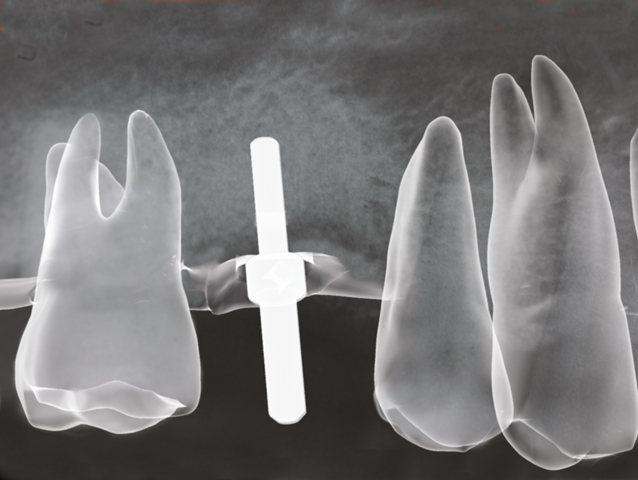

© BioHorizons Implantate bieten eine Vielzahl von Versorgungsvarianten, die Ihnen als Patient ein großes Maß an Komfort und Lebensqualität ermöglichen, wobei die für Sie "richtige" Variante individuell abgestimmt werden muss. So kann man zum Beispiel einen fehlenden Einzelzahn, den man klassischerweise durch eine Brücke ersetzt hätte, durch ein Implantat mit einer Einzelzahnkrone wieder ersetzen,

© BioHorizons

ohne dabei die evtl. gesunden Nachbarzähne beschleifen zu müssen. Eine weitere Indikation besteht darin, Ihnen wieder festen implantatgetragen Zahnersatz zu ermöglichen, wo ansonsten nur eine herausnehmbare Total- oder Teilprothese möglich gewesen wäre. Falls Sie mit dem Halt Ihrer bisherigen Prothese unzufrieden gewesen sein sollten, besteht die Möglichkeit, durch gezielten Einsatz von Implantaten den Halt und die Passung der Prothese für Sie spürbar zu verbessern.